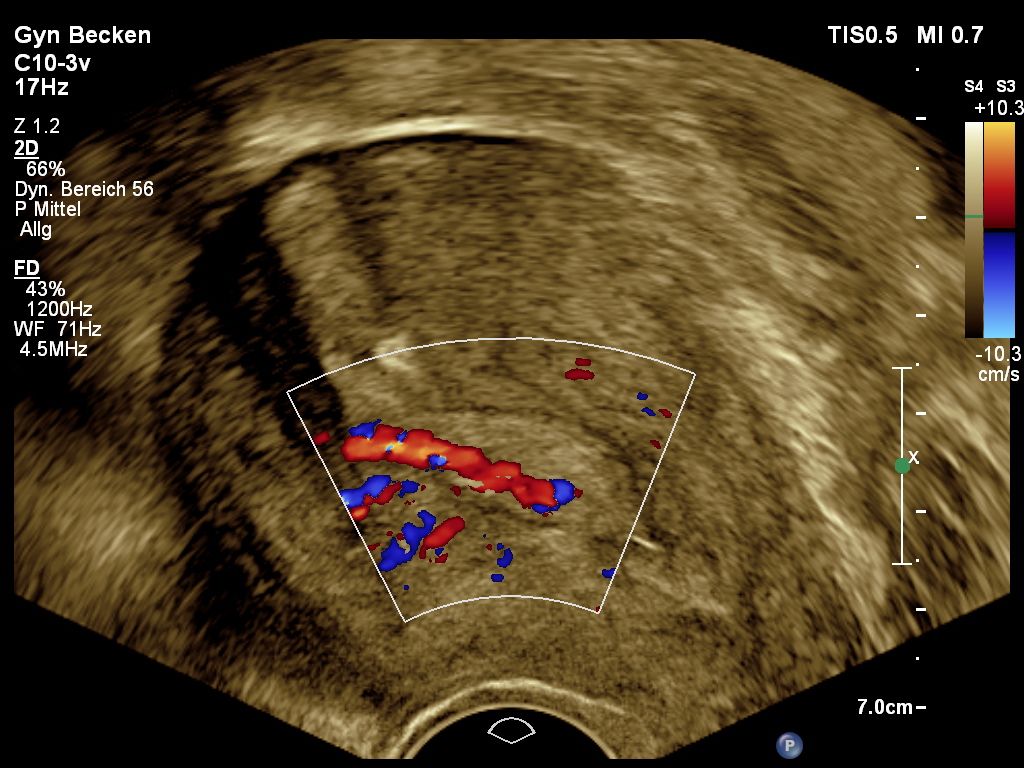

Innerhalb der Gebärmutter können sich gutartige wie bösartige Raumforderungen bilden, welche sich meist in Blutungsstörungen symptomatisch äußern. Bei gutartigen Befunden wie z.B. Polypen kann meist mit einem geringen operativen Aufwand Hilfe geleistet werden.

Unabhängig vom Ultraschall ist die Blutung nach den Wechseljahren ein frühes Verdachtsmoment für bösartige Veränderungen der Gebärmutterschleimhaut, welches weiterer, häufig operativer Diagnostik bedarf.  Der Ultraschall kann durch Messung der Dicke der Schleimhaut, durch Bestimmung der Durchblutung und Beurteilung der lokalen Struktur vorab zusätzliche Hinweise sammeln, die zu einer korrekten Erkennung bösartiger Veränderungen in über 91% der Fälle führen. Auch zur Ausbreitung der Veränderungen können wichtige Zusatzinformationen gesammelt werden. Insofern hat der Ultraschall einen festen Platz in der Diagnostik und Planung operativer Schritte bei solchen Veränderungen.

Endometriumpolyp-Doppler